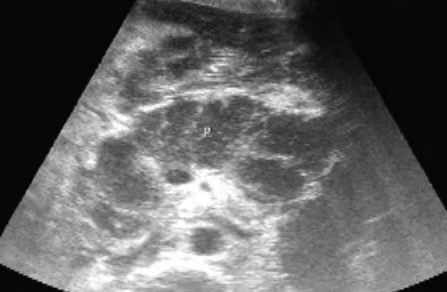

对于重症胰腺炎,其超声表现主要为:

●胰腺肿大更加明显、边缘不规则,边界不清楚,呈断续状。

●胰腺内部呈强回声、弱回声及无回声混杂的不均质改变。

●由于周围渗出及其周围组织水肿,胰腺周边可见一层弱回声带。

●胰周积液或胰腺假性囊肿形成。

●部分还可伴有胸腹腔积液。